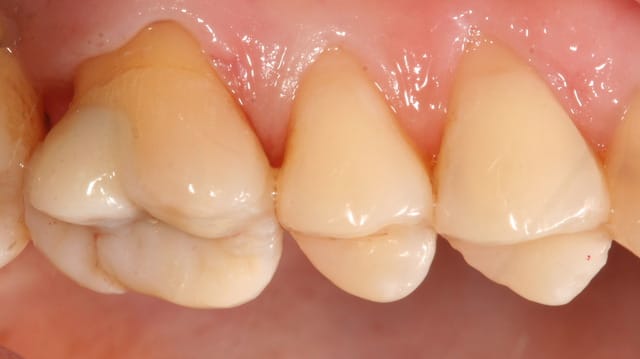

Oui... plus de 10 ans en tout cas.

La pulpite sur des onlays jamais eu. Sur des facettes/couronnes oui, environ 3-5 cas en 15 ans...

Des nécroses, plus souvent, lié je pense a l'atteinte pulpaire avant intervention. Dans ces cas je passe a travers la pièce céram et je bouche au compo

ça va être insuffisant dans des cas d'overlay, onlay a plat, ou facette

Comme pour les fraises, j'aime bien rationaliser et avoir un seul protocole de collage d'emax qui permet de tout coller très fort...